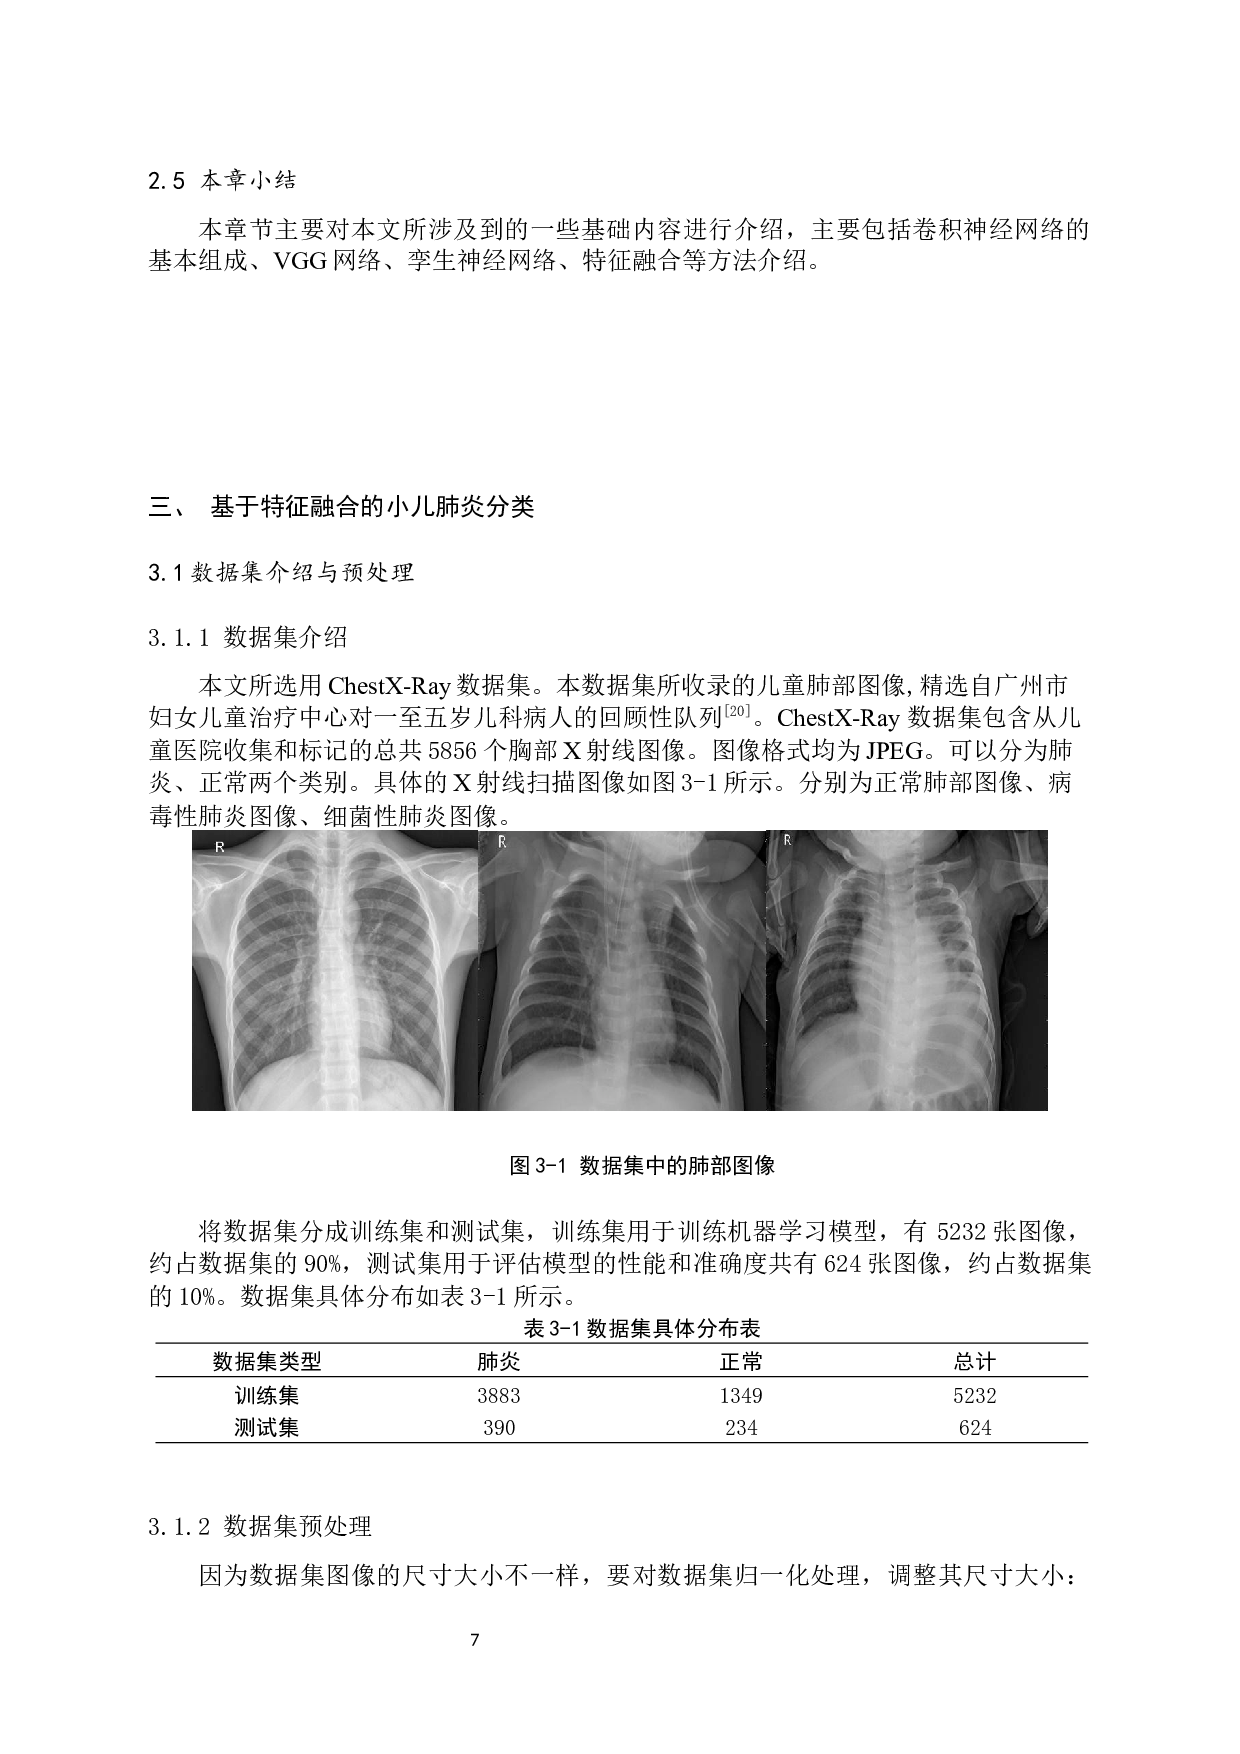

基于特征融合的小儿肺炎分类研究 作者: 王志伟 山东中医药大学智能与信息工程学院20 19 级 生物医学工程 专业 指导教师: 马志庆 摘 要 小儿肺炎是婴幼儿阶段比较普遍的一类呼吸系统病症,也是造成五周岁以内儿童夭折的重要因素。儿童本身抵抗力薄弱,一旦确诊,处理不及时,造成疾病延误,甚至会导致其他并发症。因此,及时的诊断和治疗对降低小儿肺炎致死率至关重要。医生对肺炎类型进行人工诊断的 方法 可能无法高效得出诊断结果,有 一定的局限性 。 随着技术的发展,计算机逐步具备了深度学习的能力,计算机辅助诊断技术也日渐成